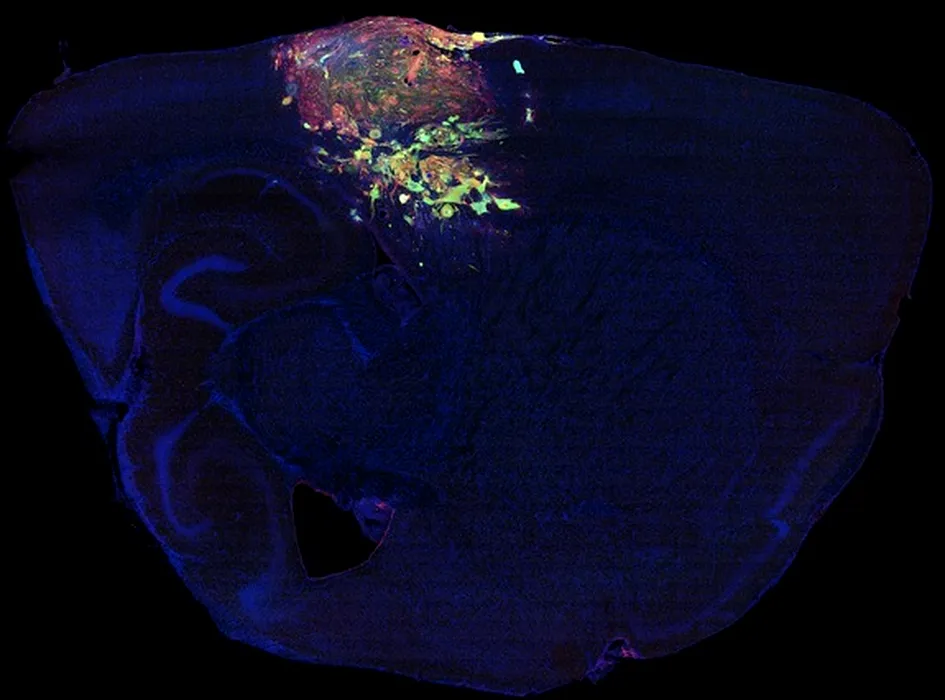

SECRETUL ascuns în aceste imagini. Cercetătorii au fost UIMIȚI